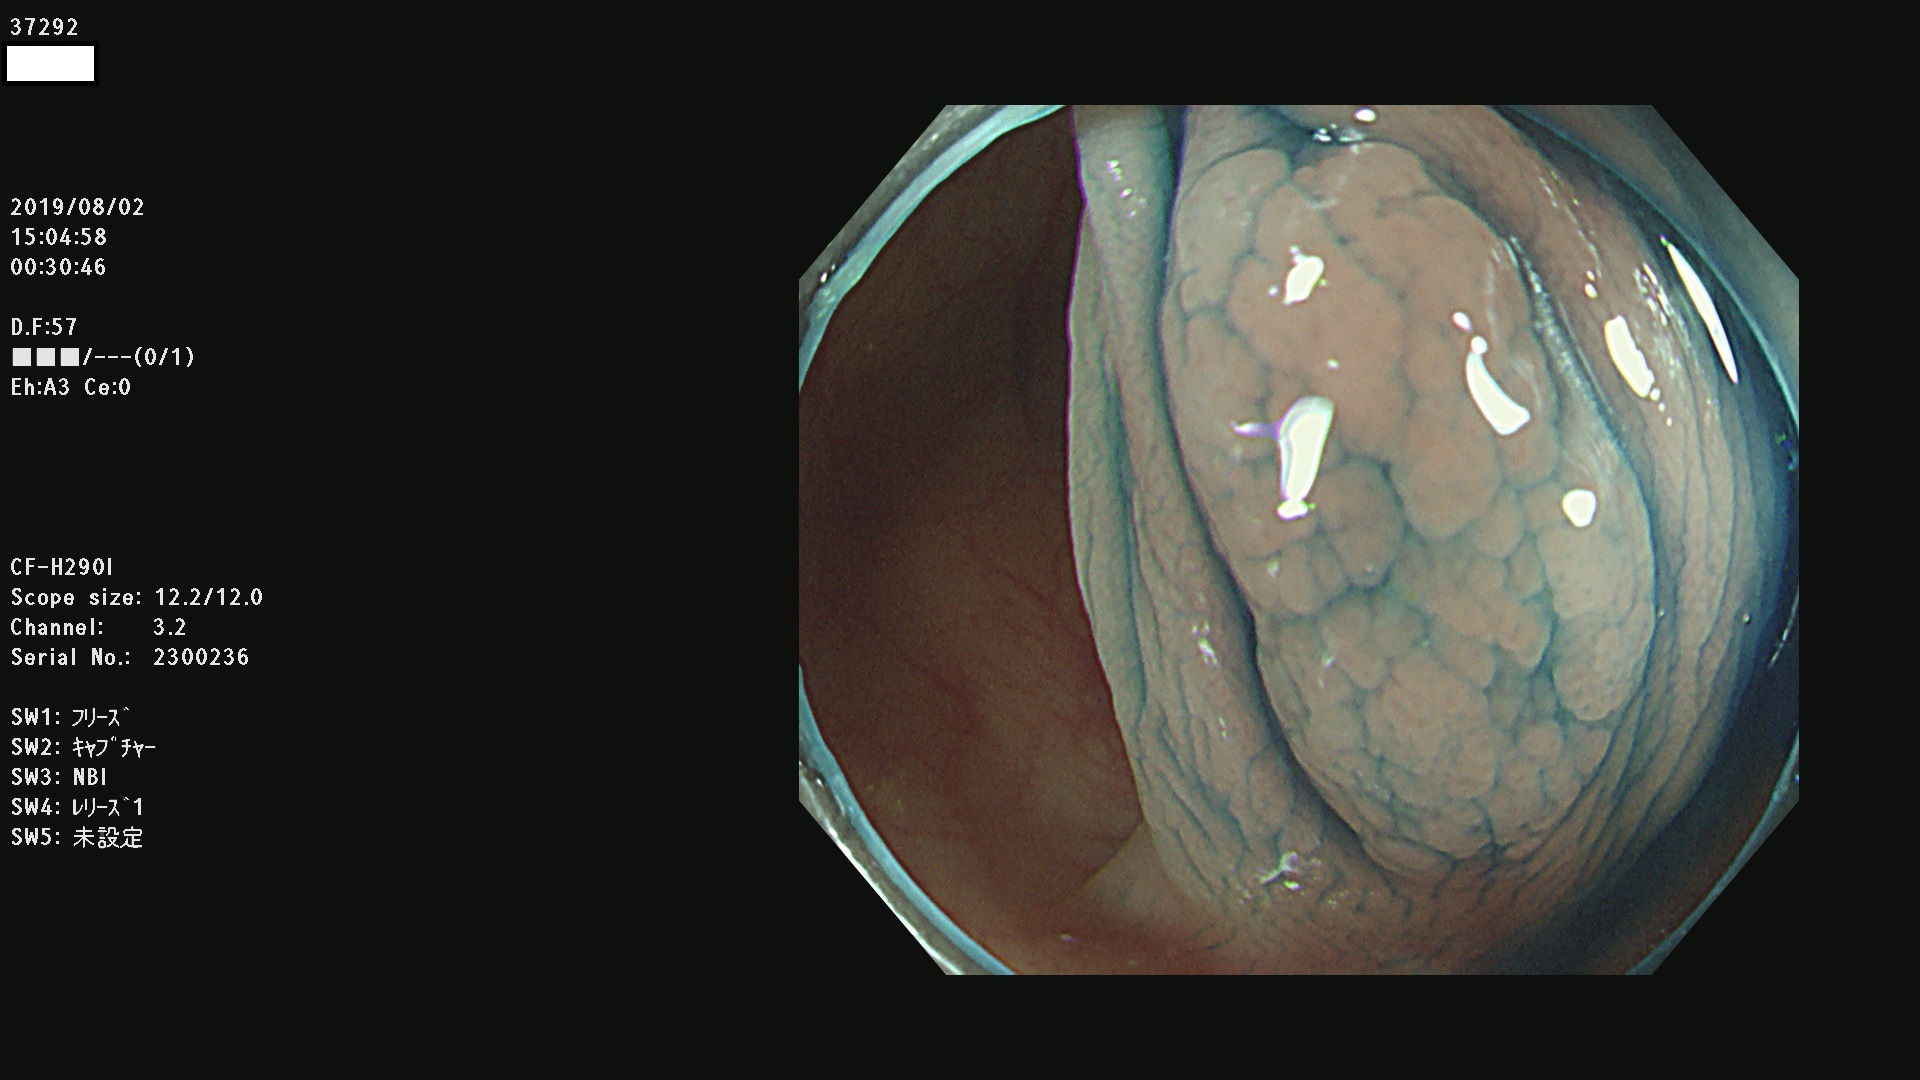

37200 37203 37204 37207 37208 37209 37210 37211 37212 37213 37214 37215 37216 37217 37220 37221 37222 37224 37225 37228 37229 37230 37232 37233 37234 37235 37236 37238 37241 37242 37243 37244 37245(SSAPのみ) 37247 37249 37250 37251 37252(SSAPのみ) 37254 37256 37257 37258 37259 37260(SSAPのみ) 37261(SSAPのみ) 37262 37263 37264 37265 37266 37267 37268(SSAPのみ) 37269 37271 37273 37274 37276 37277 37278 37279 37280 37281 37282 37284(SSAPのみ) 37285 37286 37288 37289 37290 37292 37293 37295 37296 37297(SSAPのみ)

発見困難で危険性の高い平坦型病変(上記100名より抽出)